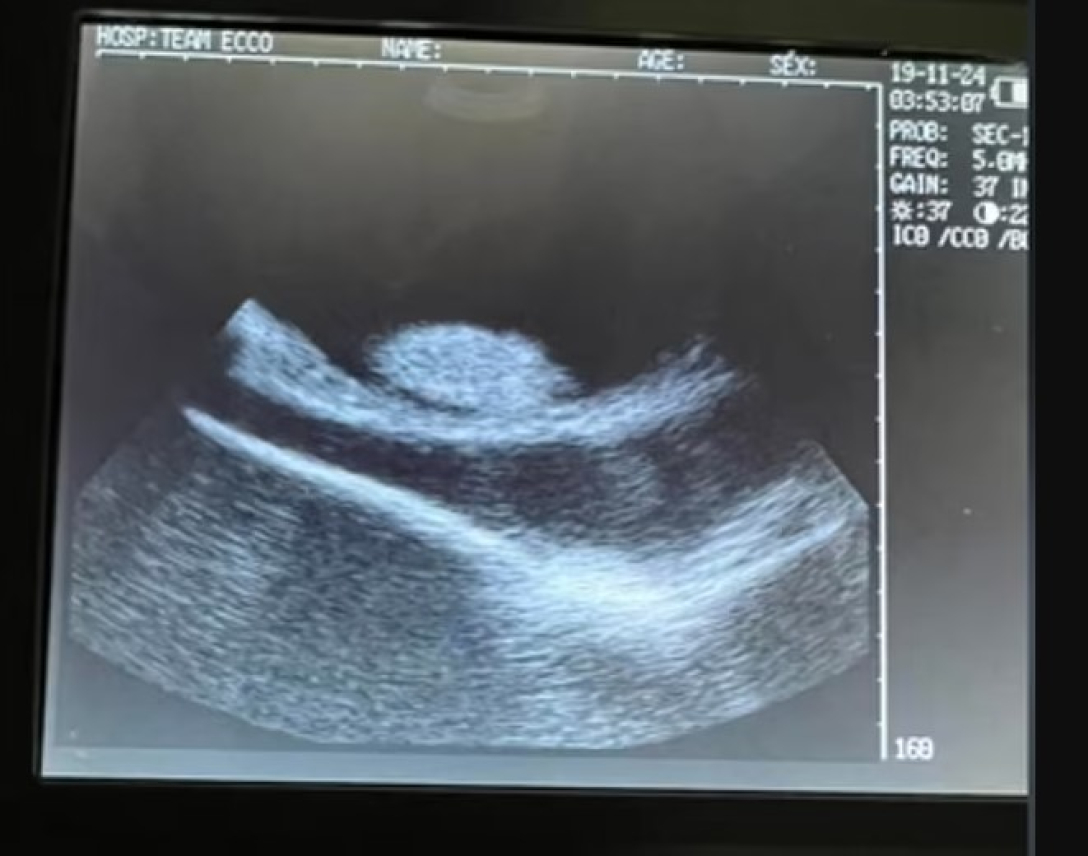

скат шарлотта узи

В качестве доказательств беременности Шарлотты сотрудники аквариума предоставили снимки УЗИ

Фото: Aquarium & Shark Lab